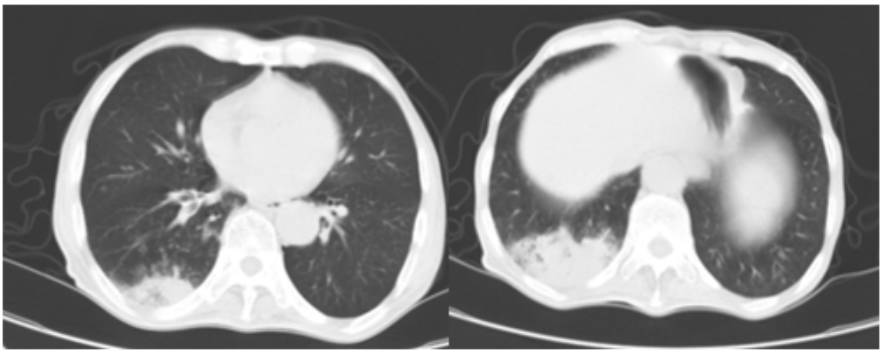

NMD可引起上气道肌肉功能障碍、胸壁畸形/脊柱侧弯、吸气肌功能障碍、呼气肌功能障碍、吞咽困难、呼吸中枢功能障碍,进而引起阻塞性呼吸睡眠暂停、限制性通气功能障碍、气道廓清障碍以及呼吸道反复感染,最终导致出现通气功能障碍和换气功能障碍,进而引起呼吸功能障碍。进行性神经肌肉无力患者通常经过四个阶段的连续过渡期: 第一阶段, 正常通气; 第二阶段, 在急性疾病、手术等生理应激期间有通气不足的风险; 第三阶段, 夜间肺泡通气; 第四阶段, 夜间和昼夜肺泡通气不足(持续性呼吸衰竭)。通常RICU内的患者往往处于持续的呼吸衰竭状态,根据患者是Ⅰ型还是Ⅱ型呼吸衰竭再判断其是通气功能障碍还是换气功能障碍,然后再根据上图倒推患者是否存在NMD可能引起的能导致呼吸系统功能障碍的器官功能障碍。对于可疑NMD患者, 往往有两大特点: ①消瘦: 如果是不想吃, 则需要判断患者有无心理问题; 如果是因为担心呛咳而不敢吃, 需要评估有无吞咽障碍; 如果是吃了也不胖, 考虑是否有慢性消耗性疾病, 例如肿瘤等; ②无力: 可以请神经科医生会诊, 通过定位诊断、肌电图、肌肉活检、影像学、生化、基因检测等方法明确诊断。(1)定位诊断:有助于缩窄疾病范围。值得关注的是,其中有相当一部分神经病变与肿瘤相关,例如:中枢神经系统/上层运动神经元病变可能与软脑膜恶性肿瘤有关,前角细胞病变可能与副肿瘤有关,混合神经元病变则可能与恶性浸润和副肿瘤性疾病有关。(3)肌肉活检: 对于病因不明的肌无力患者, 肌肉活检仍然是重要的诊断性检查。肌肉活检一直被认为是诊断肌病的基石, 也是诊断几类肌肉疾病的必要条件, 包括: 遗传性疾病(例如: 肌营养不良症、强直性肌营养不良症), 获得性肌病(如炎症性肌病), 中毒性和药物性肌病。(4)生化检查:部分风湿免疫相关疾病以及代谢性遗传病需要借助于生化检查进行辅助诊断,例如肌酸激酶、风湿免疫相关检查,GAA酶活性检测(庞贝病)等。(5)基因检测:目前已知有超过600种单基因疾病会导致NMD,因此可以通过基因检测的方法识别NMD。(6)影像学:MRI能够评估肌肉脂肪含量的变化,有助于诊断外周单神经病和多发性神经病以及运动神经元病变,以及诊断和随访各种原发性肌肉疾病(包括获得性和遗传性肌病)。神经肌肉超声用于NMD原发病诊断和评估,有助于多发性神经病的鉴别诊断。当明确诊断或高度怀疑NMD时,进一步进行评估是后续干预治疗的基础,包括症状、呼吸功能、肌肉和运动能力、吞咽功能、营养和心理状况。(1)呼吸功能评估:2019年欧洲呼吸学会(ERS)发布了关于休息和运动时呼吸肌测试的声明,其中阐述了横膈肌功能障碍的评估流程(下图所示)。(2)肌肉功能的评估:MRC评分可用来评估肌力,对腕、肘、肩、踝、膝及髋6个关节双侧12个肌群进行评分,总分为60分。当MRC总分<48分即可诊断为ICU获得性肌无力(ICU-AW)。男性握力<11 kg,女性握力<7 kg,则可判断为肌肉衰弱。等速试验是NMD患者综合评估和康复的重要一环。研究已经证明了它在提供临床相关信息方面的有效性。当与完整的病史、体格检查和功能评估相结合时,等速测试和运动可以成为临床医生评估、康复和增强NMD患者的宝贵工具。此外,床旁对运动心肺功能测试(CPET)在重症患者肌肉评估中也能发挥重要作用。对于一些NMD可以开展病因治疗(下图所示),例如:吉兰巴雷综合征、重症肌无力、急性炎症性肌病、ICU获得性神经肌肉功能障碍、神经源性疾病、肌病。无论病因能否消除,都可以进行物理治疗,对患者进行膈式呼吸、胸廓松动、呼吸肌训练和膈肌起搏。此外,气道廓清技术在临床中应用广泛,其在清除呼吸道分泌物、改善呼吸困难症状、预防和减少呼吸道感染等方面有显著作用。可以进行姿势纠正、核心肌群锻炼,外周骨骼肌训练,以及间歇性低强度的有氧运动,也有助于改善NMD患者的预后。启动无创正压通气(NPPV)的标准:①症状:乏力、呼吸困难、晨起头痛等症状;②下列指标之一:a. PaCO2>45 mmHg;b. 夜间血氧饱和度<88%持续大于5 min;c. 最大吸气压(MIP)<60 cmH2O或用力肺活量(FVC)<50%预计值。启动NPPV的禁忌证:呼吸道梗阻、分泌物潴留未能控制、不能配合、不能达到咳嗽最大流速(PCF)及无合适面罩或鼻罩可供选择等。当患者有NPPV禁忌证或NPPV不能满足通气需求时才考虑使用有创机械通气。机械通气支持在重症肌无力患者中通常是短期的,在吉兰巴雷综合征患者中通常是长期的,在遗传性或退行性肌肉疾病中是永久性的。吉兰巴雷综合征患者插管的临界值为肺活量<20 ml/kg(体重)、MIP<-30 cmH2O和最大呼气压(MEP)<40 cmH2O(“20/30/40规则”)。一般情况:患者,男性,73岁,身高168 cm,体重40 kg,主诉“呼吸困难半月余,加重5天”。现病史:半个月前出现呼吸困难,轻微活动即有气短等症状,有痰不易咳出。5天前加重,严重时不能平卧,就诊于我院急诊,行肺CT检查提示肺气肿、右肺下叶炎症,给予氧疗、头孢曲松抗感染治疗及雾化吸入、解痉平喘治疗。患者症状未见明显好转,血气分析提示PaCO2 71 mmHg,PaO2 130 mmHg。为求进一步诊治,收入我科。病程中无发热,伴食欲减退,乏力。既往史: 吸烟史40年, 20支/日, 已戒, 体健。查体:T 36.7℃,P 87次/min,R 18次/min,BP 119/83 mmHg,身高168 cm,体重40 kg。BMI 14.2 kg/m2,消瘦,意识清楚,双肺呼吸音粗,可闻及散在湿啰音。心率87次/min,律齐,无额外心音及杂音,腹平软,无压痛、反跳痛及肌紧张,肝脾肋下未触及,双下肢无水肿,四肢肌力3级。辅助检查:①肺CT:气管、右主支气管及右肺下叶支气管腔内黏液潴留,支气管炎,双肺散在炎症,右肺下叶为著,局限性肺气肿。②心脏超声:主动脉瓣钙化,主动脉瓣轻度反流。③血气分析:PaO2 71 mmHg,PaCO2 61 mmHg。④D-二聚体0.66 mg/L,BNP 456 pg/ml。⑤血常规:WBC 10.38×109/L,NEU% 87%,Hb 142 g/L。⑥膈肌超声:呼气末膈肌厚度0.07 cm,膈肌活动度0.67 cm,提示膈肌萎缩,膈肌活动度下降。握力计:17 kg,肌肉力量下降。初步诊断:双肺肺炎,Ⅱ型呼吸衰竭,慢性阻塞性肺疾病?CO2升高:Ⅱ型呼吸衰竭原因——慢阻肺?咳痰能力差,肌力下降,营养状态差。追问病史:患者1年前无明显诱因出现乏力、食欲下降、消瘦。就诊于当地医院行胃肠镜及化验(具体诉不清)检查未见异常,无特殊处置,乏力、消瘦症状逐渐加重,偶有呛咳。3个月前,自觉胸闷、气短,就诊于延边医院,行肺CT提示少许炎症,肝肾功能未见明显异常。于当地医院给予抗生素(头孢,具体不详)治疗1周,症状未见明显好转。近半个月患者体力明显下降,胸闷气短症状加重,轻微活动即有呼吸困难,有痰不易咳出。5天前呼吸困难加重,严重时不能平卧,就诊于我院急诊,肺CT提示肺气肿、右肺下叶炎症,给予氧疗、头孢曲松抗感染治疗及雾化吸入、解痉平喘治疗。患者症状未见明显好转,血气分析提示PaCO2 71 mmHg,PaO2 130 mmHg。为求进一步诊治,收入我科。否认慢性咳嗽、咳痰等呼吸系统疾病症状及病史。考虑是否为限制性通气功能障碍?患者床旁肺功能检查结果:极重度限制性通气功能障碍,FVC占预计值21.6%;吸气肌肌力下降,MIP为14 cmH2O;呼气肌肌力下降,MEP为24 cmH2O。因此考虑患者存在NMD相关问题。消瘦、肌无力:请神经内科会诊,诊断依次为:肌无力综合征(癌性居多);危重症性周围神经肌病;运动神经元综合征;重症肌无力。重症肌无力4项抗体、乙酰胆碱受体抗体、电压门控钾通道自身抗体、副肿瘤抗体14项均为阴性;肌电图无异常;颅脑CT无明显异常。肿瘤:肺CT、腹部CT未见肿瘤改变;当地胃肠镜未见异常;肿瘤标志物、副肿瘤抗体阴性;PET-CT未做。心理科会诊意见:进食差不能排除心理因素,暂予草酸艾司西酞普兰5 mg/早治疗。尽管该患者并未确诊NMD,但仍然不能排除,积极康复治疗。康复目标:改善患者营养状态,增强肌肉功能,提高气道清洁能力。营养支持方案:患者吞咽功能下降,食欲差,留置胃管,给予肠内营养;营养代谢车测评患者能量需求,能量输送增加至测量到能量消耗的80%~100%。逐步每日输送1.3 g/kg蛋白质;吞咽功能康复。针对外周骨骼肌功能障碍:渐进式肢体活动,有氧耐力训练,力量训练。康复治疗后,患者病情一度有所改善。但最终突发意识不清,呼之不应,呼吸心跳骤停,气管插管,心肺复苏,复律。支气管镜下见大量黄白色分泌物。家属放弃抢救。